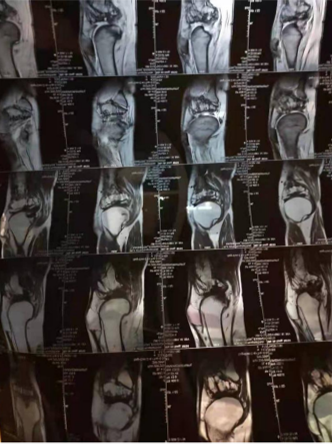

这是70多岁李妈妈的膝关节影像,两年前,由于老年关节退行性病变,双膝疼得走不了路,且无法下蹲。

去年5月至8月,连续四个月,老人进行了关节腔靶向注射加静脉回输干细胞的治疗后,很快就能正常走路,双膝可以正常下蹲,也不疼了。